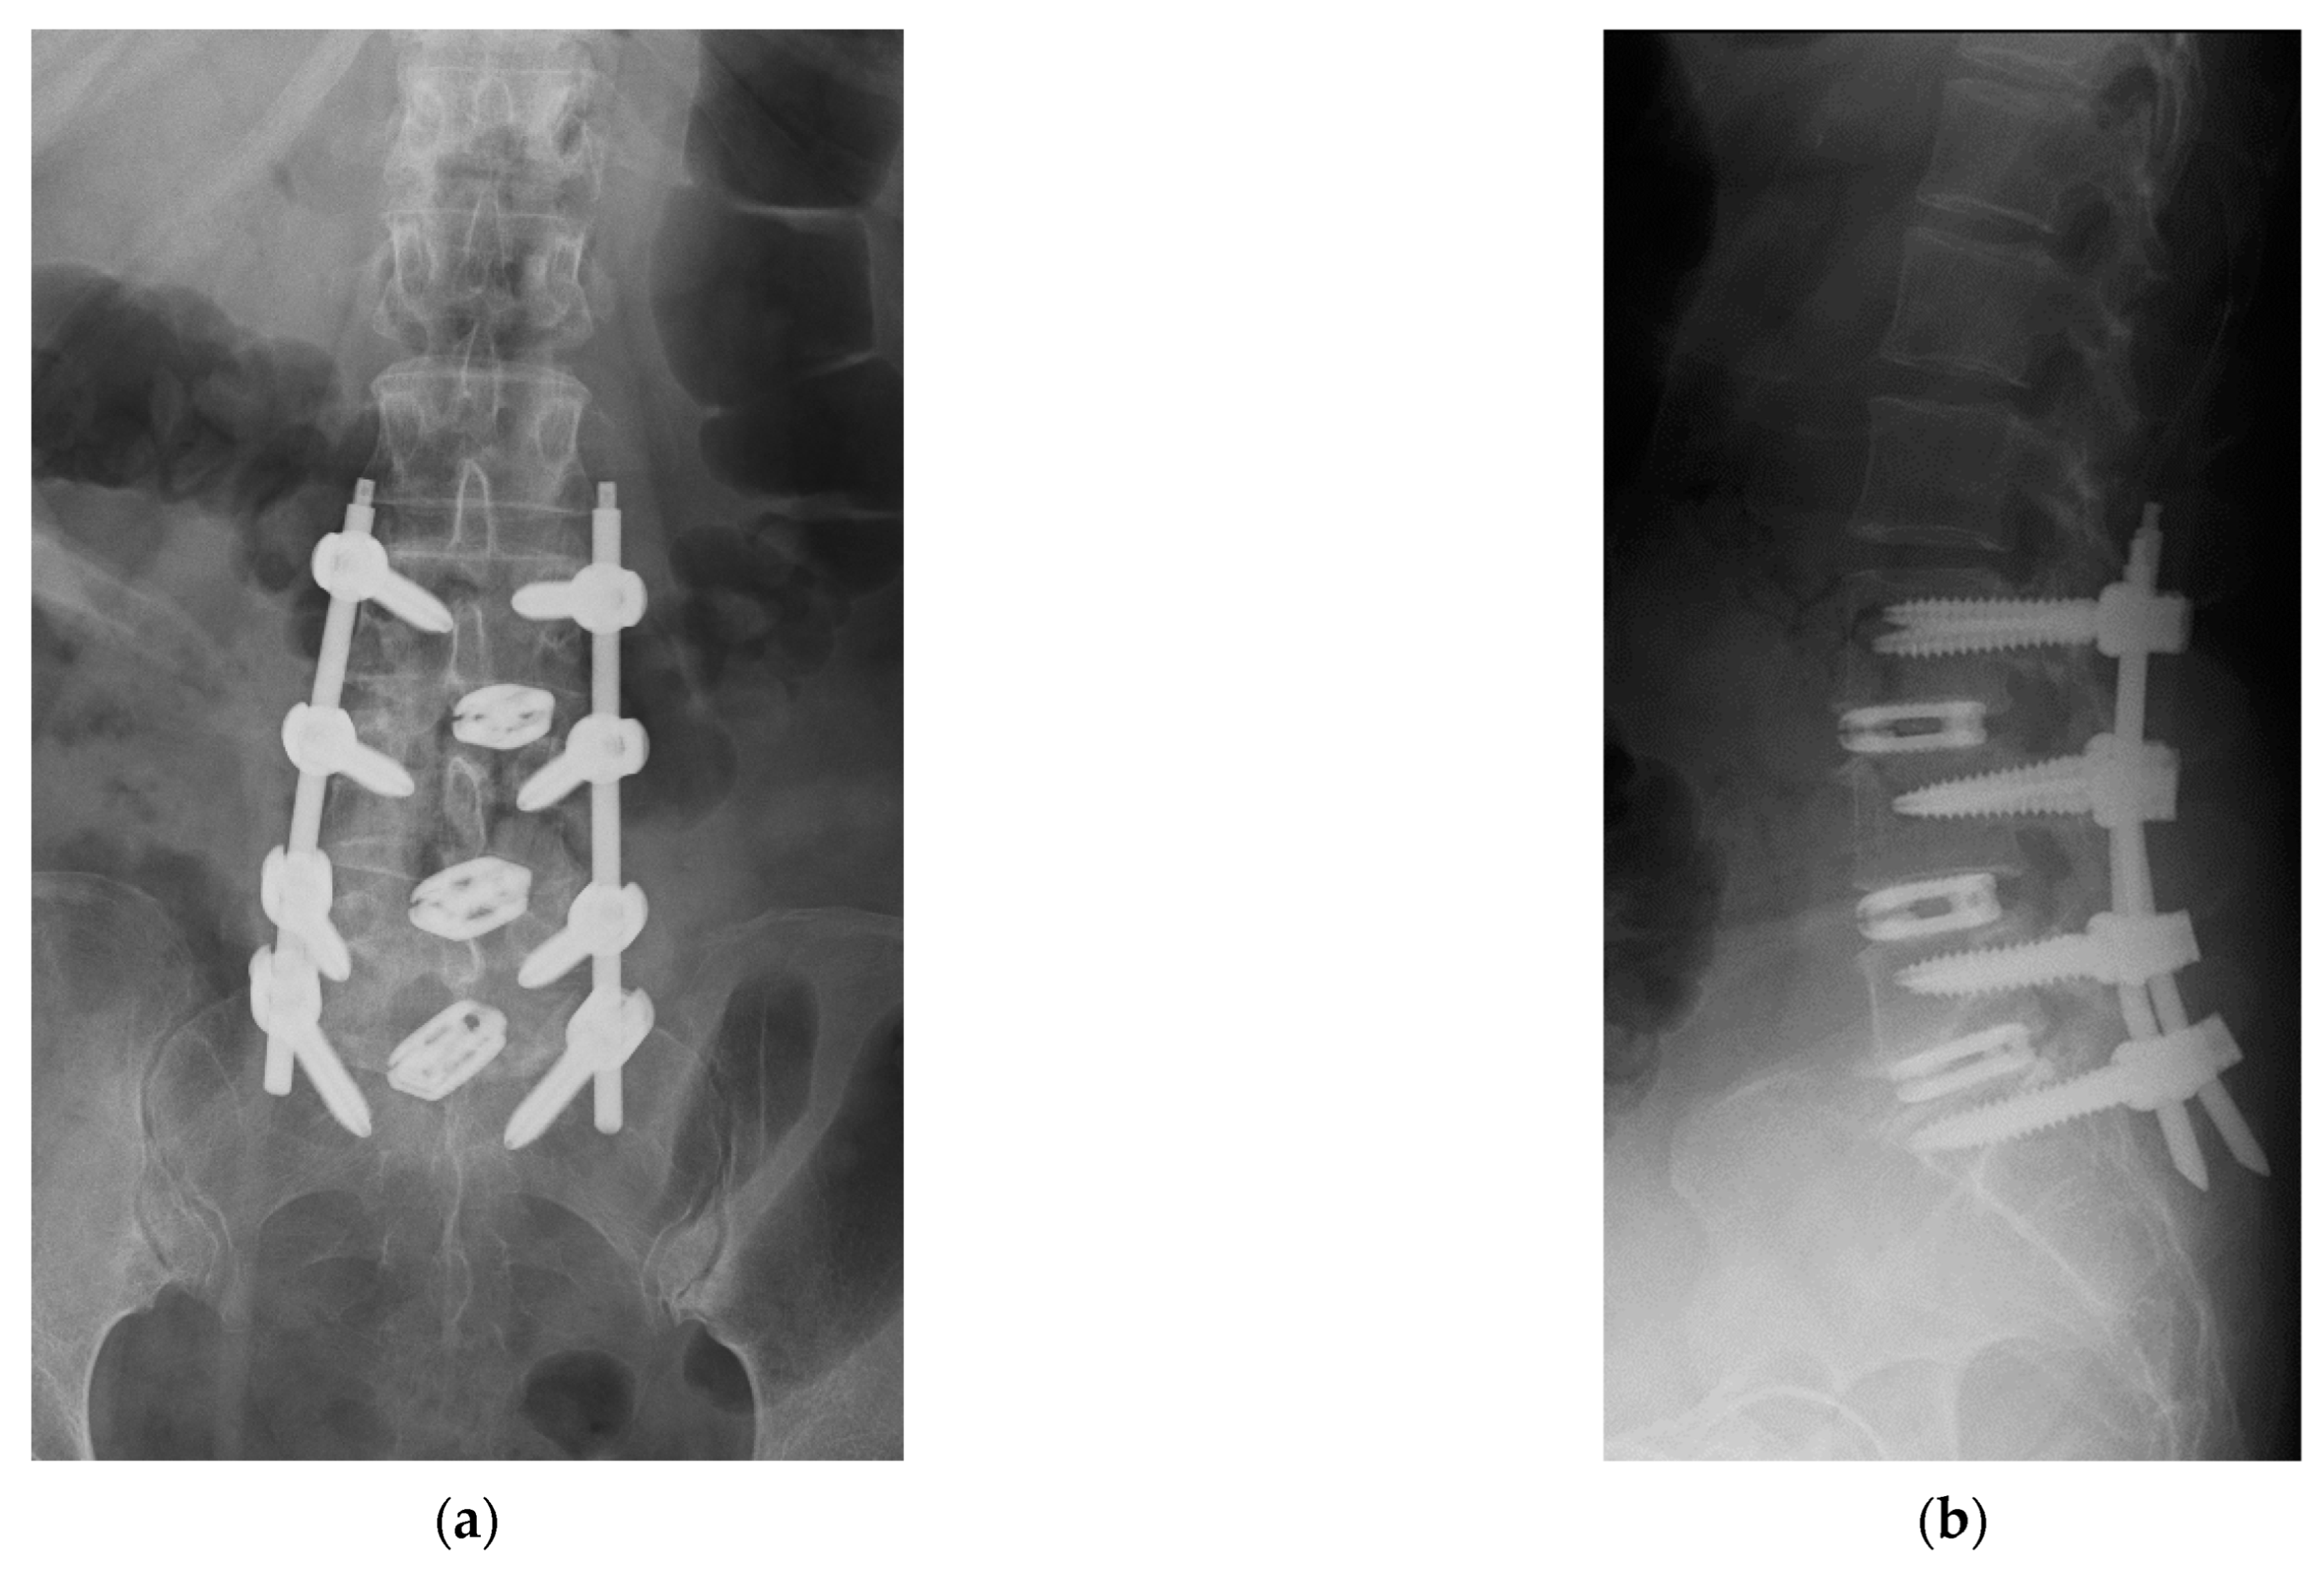

4. Case Example

4.1. Case 1: Madam M

4.2. Case 2: Madam R

4.3. Case 3: Madam M